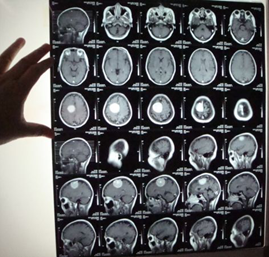

MRI:右顶窦镰旁占位、考虑右顶窦镰旁脑癌(附件如下:)。

诊断:右侧顶窦镰旁脑癌